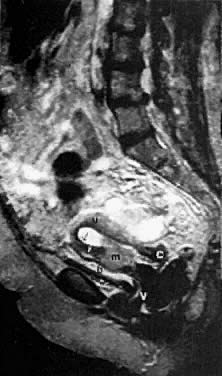

Fig. 22. Sagittal T2-weighted MRI in a patient with a stage IA endometrial carcinoma shows replacement of the lower two thirds of the hyperintense endometrium by an inhomogeneous medium-intensity irregular mass ( m) that invades the deeper layer of the myometrium anteriorly. ( u, uterus; c, cervix; v, vagina; b, bladder; black arrow, endometrium; white arrow, uterine junctional zone.)